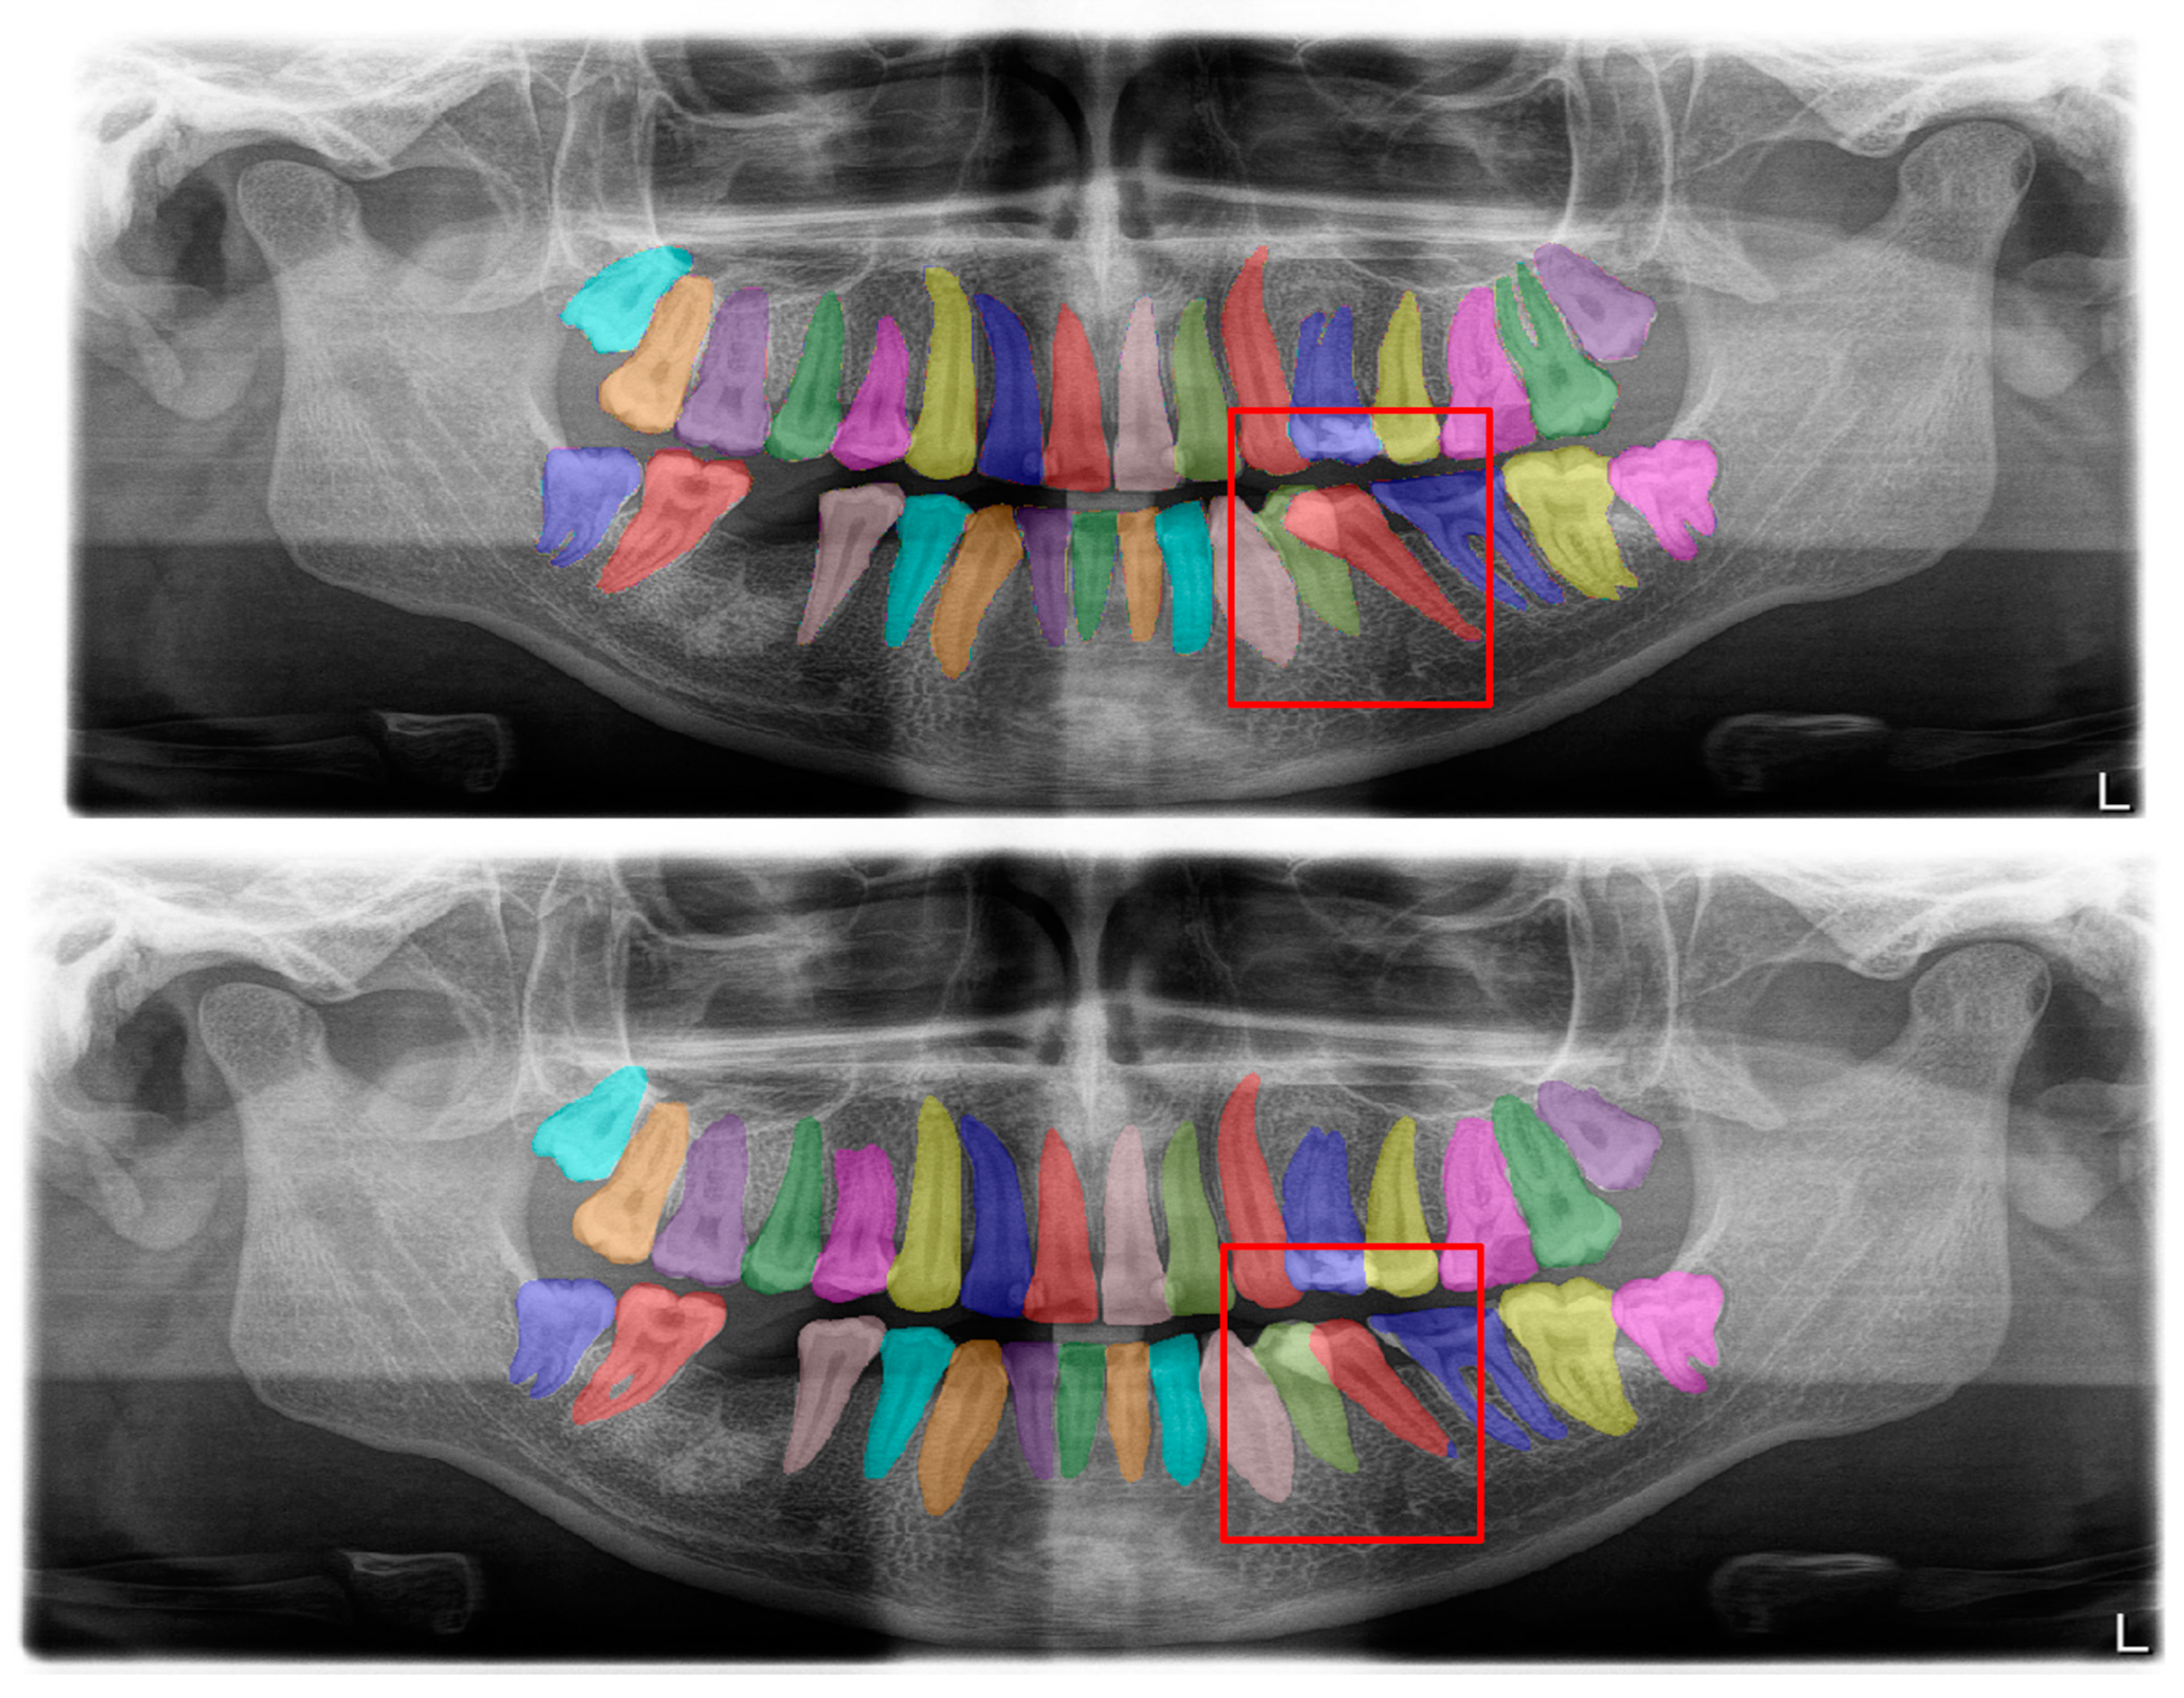

Figure 2.

Automatic segmentation of the teeth. Manual segmentation (upper image) and automatic segmentation (lower image) can be seen above. Each tooth has a unique label according to FDI World Dental Federation notation.

The calculated DSC values across all OPGs (Table 1) were 0.85 for the teeth, 0.88 for dental caries, 0.87 for dental restorations, 0.93 for crown–bridge restorations, 0.94 for dental implants, 0.78 for root canal fillings, and 0.78 for residual roots. Manual segmentations and successful automatic segmentations of the model are given in Figure 2, Figure 3, Figure 4, Figure 5, Figure 6 and Figure 7, while common erroneous automatic segmentations with the most possible reasons are given in Figure 8, Figure 9, Figure 10, Figure 11 and Figure 12.

In tooth segmentation, it has been observed that the segmentation of the root apices of the maxillary third molars, especially those that are impacted in a vertical position, in cases where the root apices are superimposed with the maxillary sinus floor, is incorrectly automatically segmented at different degrees. This is one of the reasons for erroneous segmentation, which reduced the Dice score in our study, albeit only by a small amount. The superposition, which we have seen especially in the premolar region on OPGs, actually shows a limitation of OPGs, not a deficiency of our model (Figure 9). The primary reason why our model could not achieve a perfect result in tooth segmentation is because it is almost impossible to avoid superimpositions on OPGs, especially in premolar teeth, and also because patients with crowding are included in the study. Several studies excluded patients with orthodontic problems; however, one of our main goals was to evaluate the success of our model in the general population, since there will not be any exclusions in dental clinics [91,92].